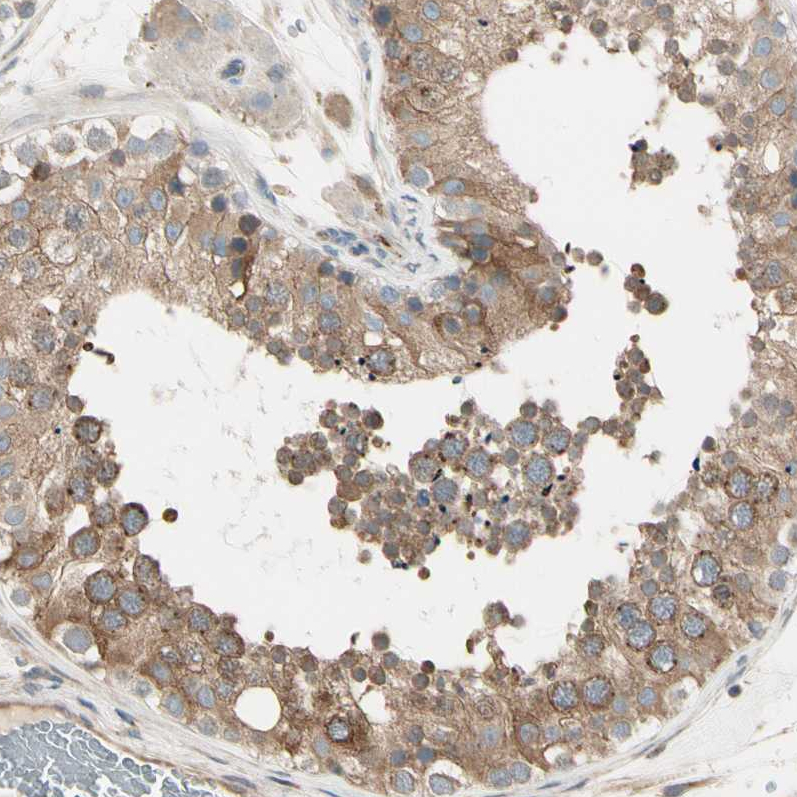

Immunohistochemical staining of human pancreas shows strong cytoplasmic positivity in exocrine glandular cells.